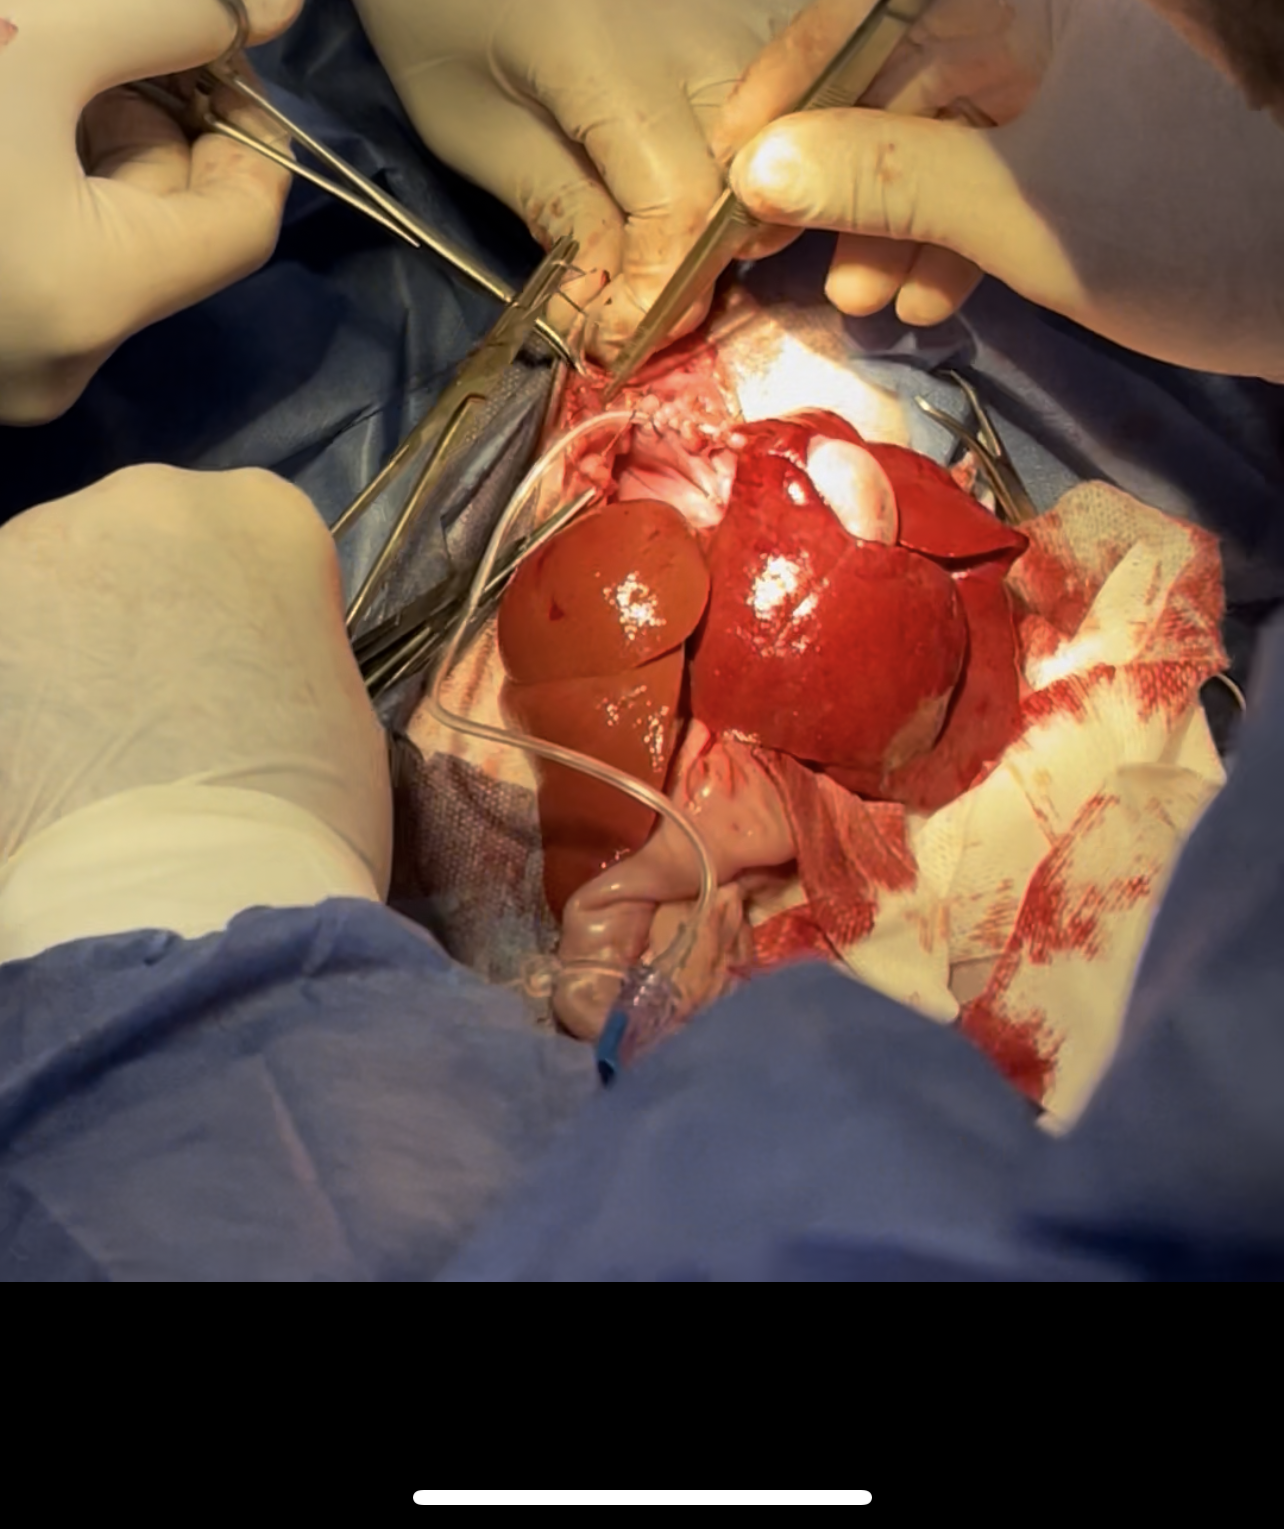

Stomach and intestines exteriorized and liver can be seen inside the thoracic cavity

Liver is exteriorized

Hernia is sutured with the tube passing through to extract the remaining air

3 way stop catheter is used for faster air extraction